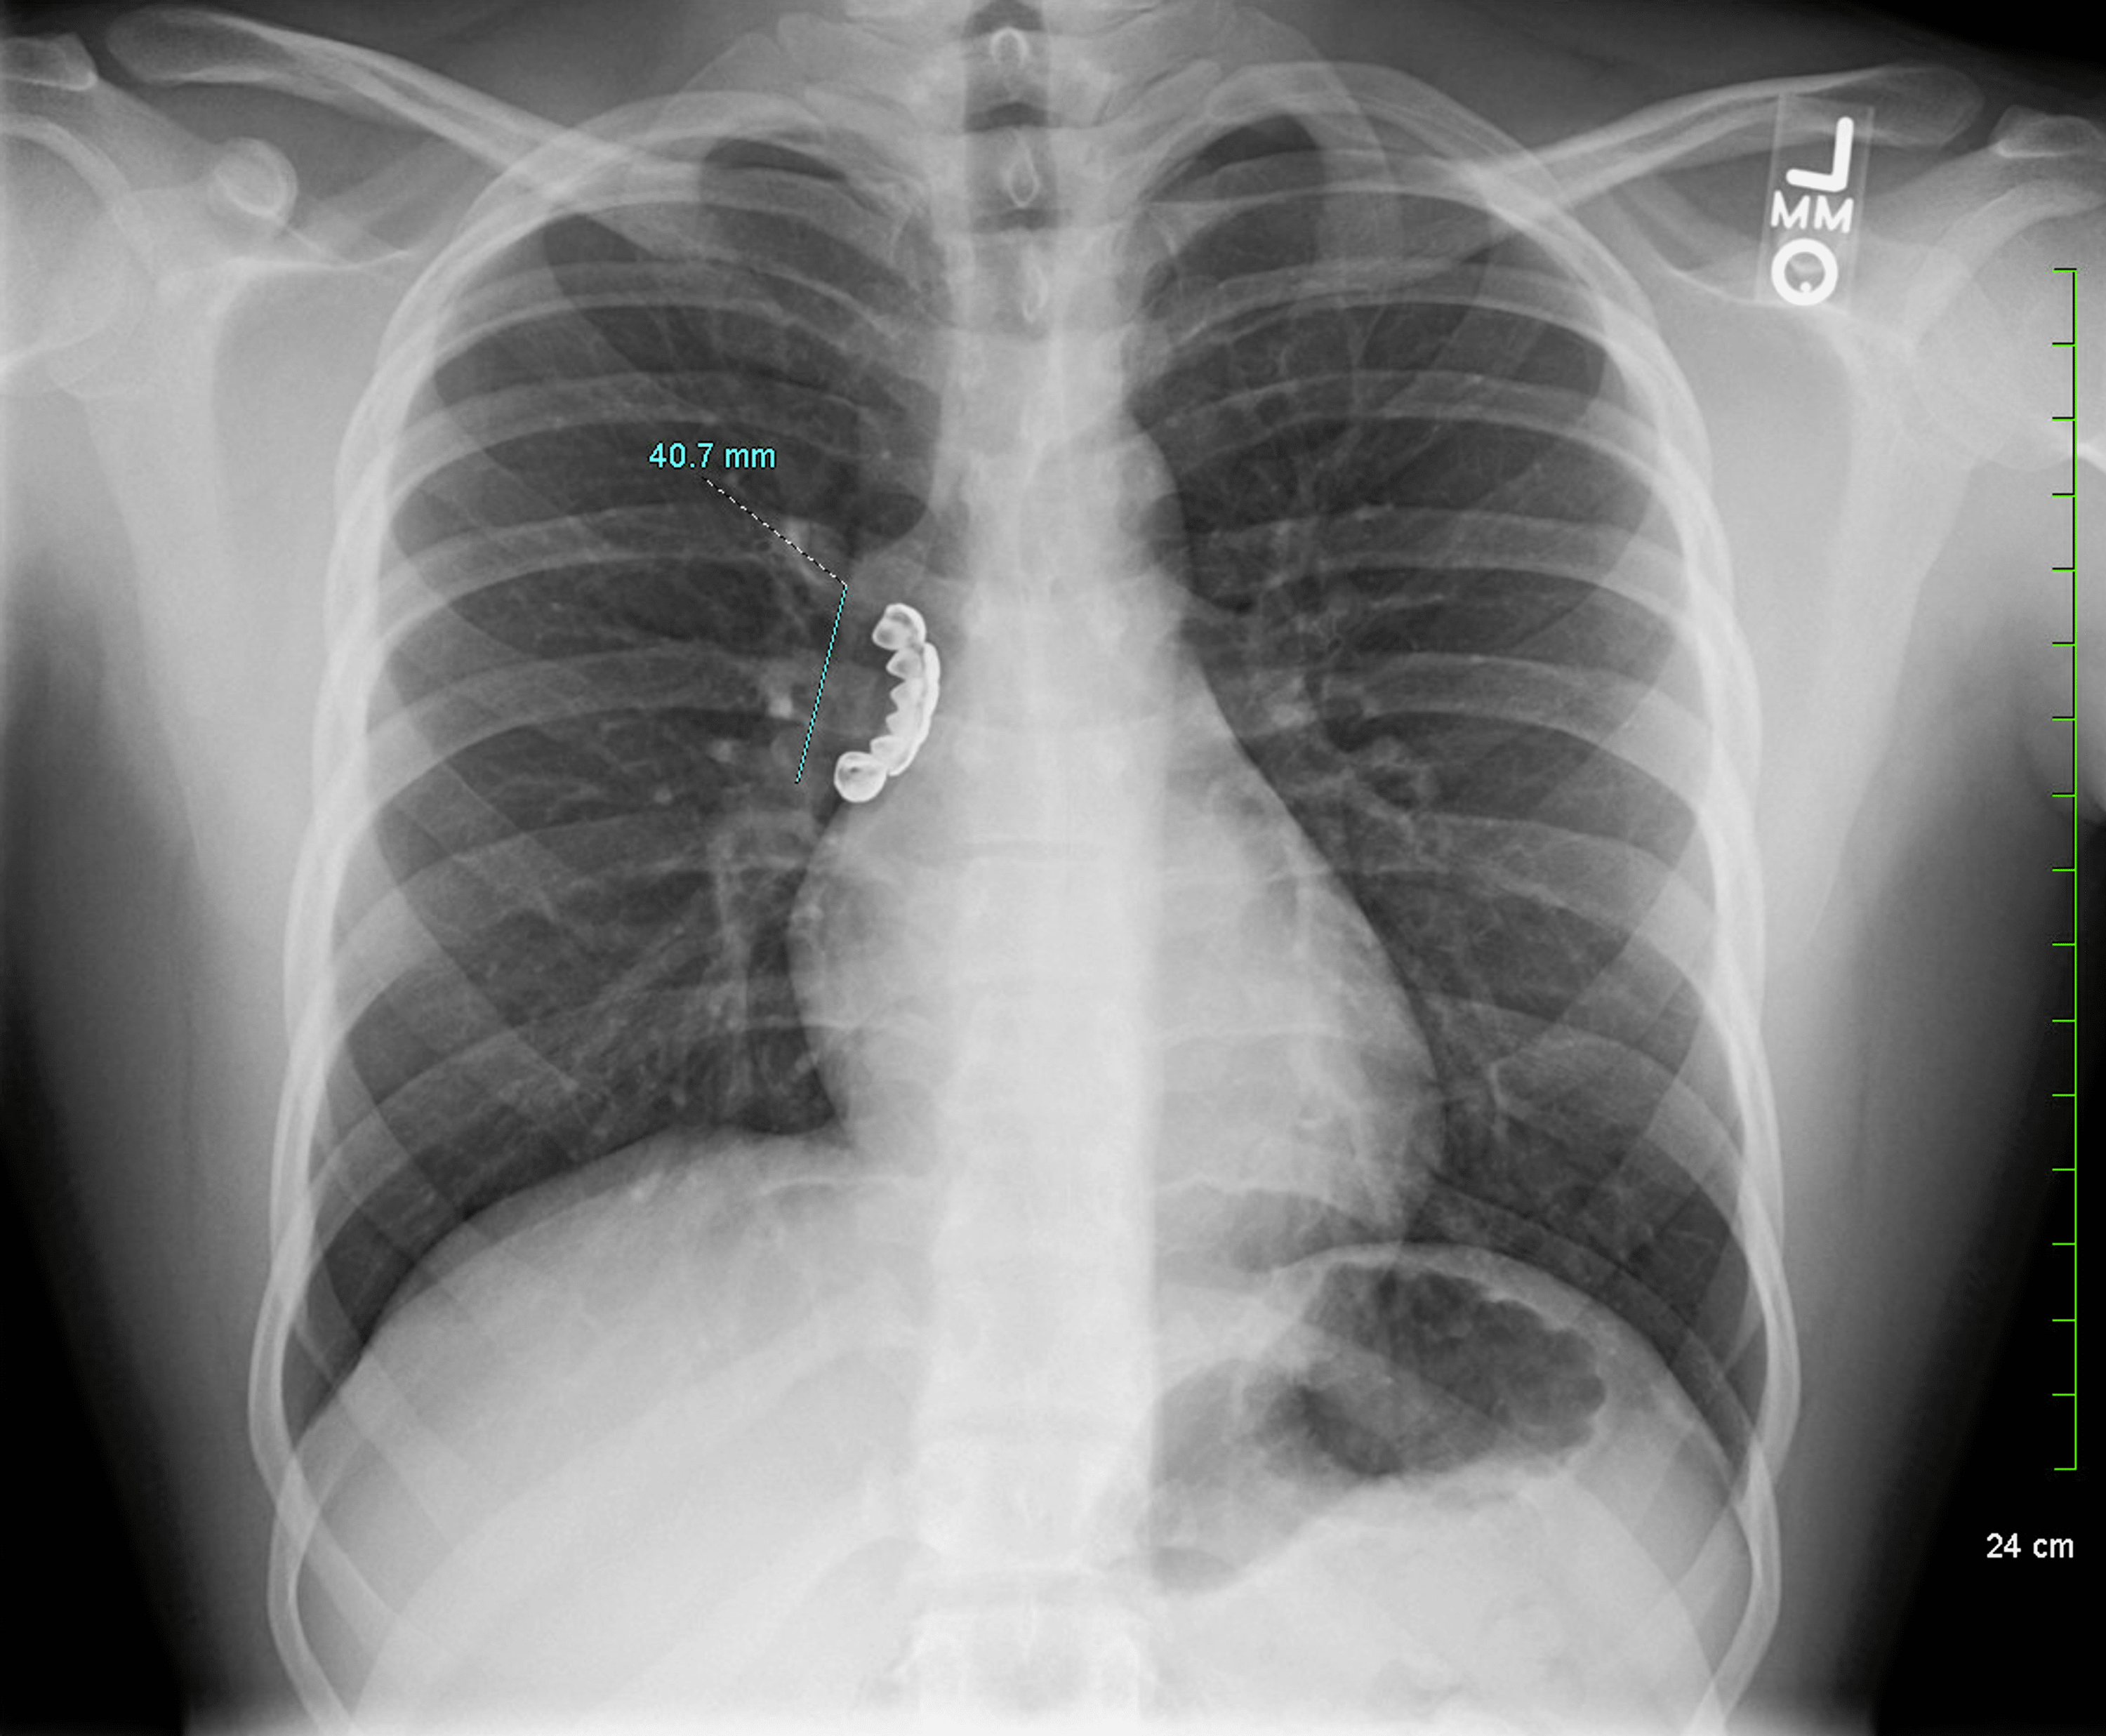

The lung Xray performed three weeks after tooth extraction shows the Dental Drill Lung Abdelghani used the latest technology, the ion robotic bronchoscope, which is usually used to get lung tumors. the ct scan tells the shocking story: the ct scan tells the shocking story: a routine trip to the dentist was anything but normal — after an illinois man inhaled the dentist’s drill bit and had to go. the. Dental Drill Lung.